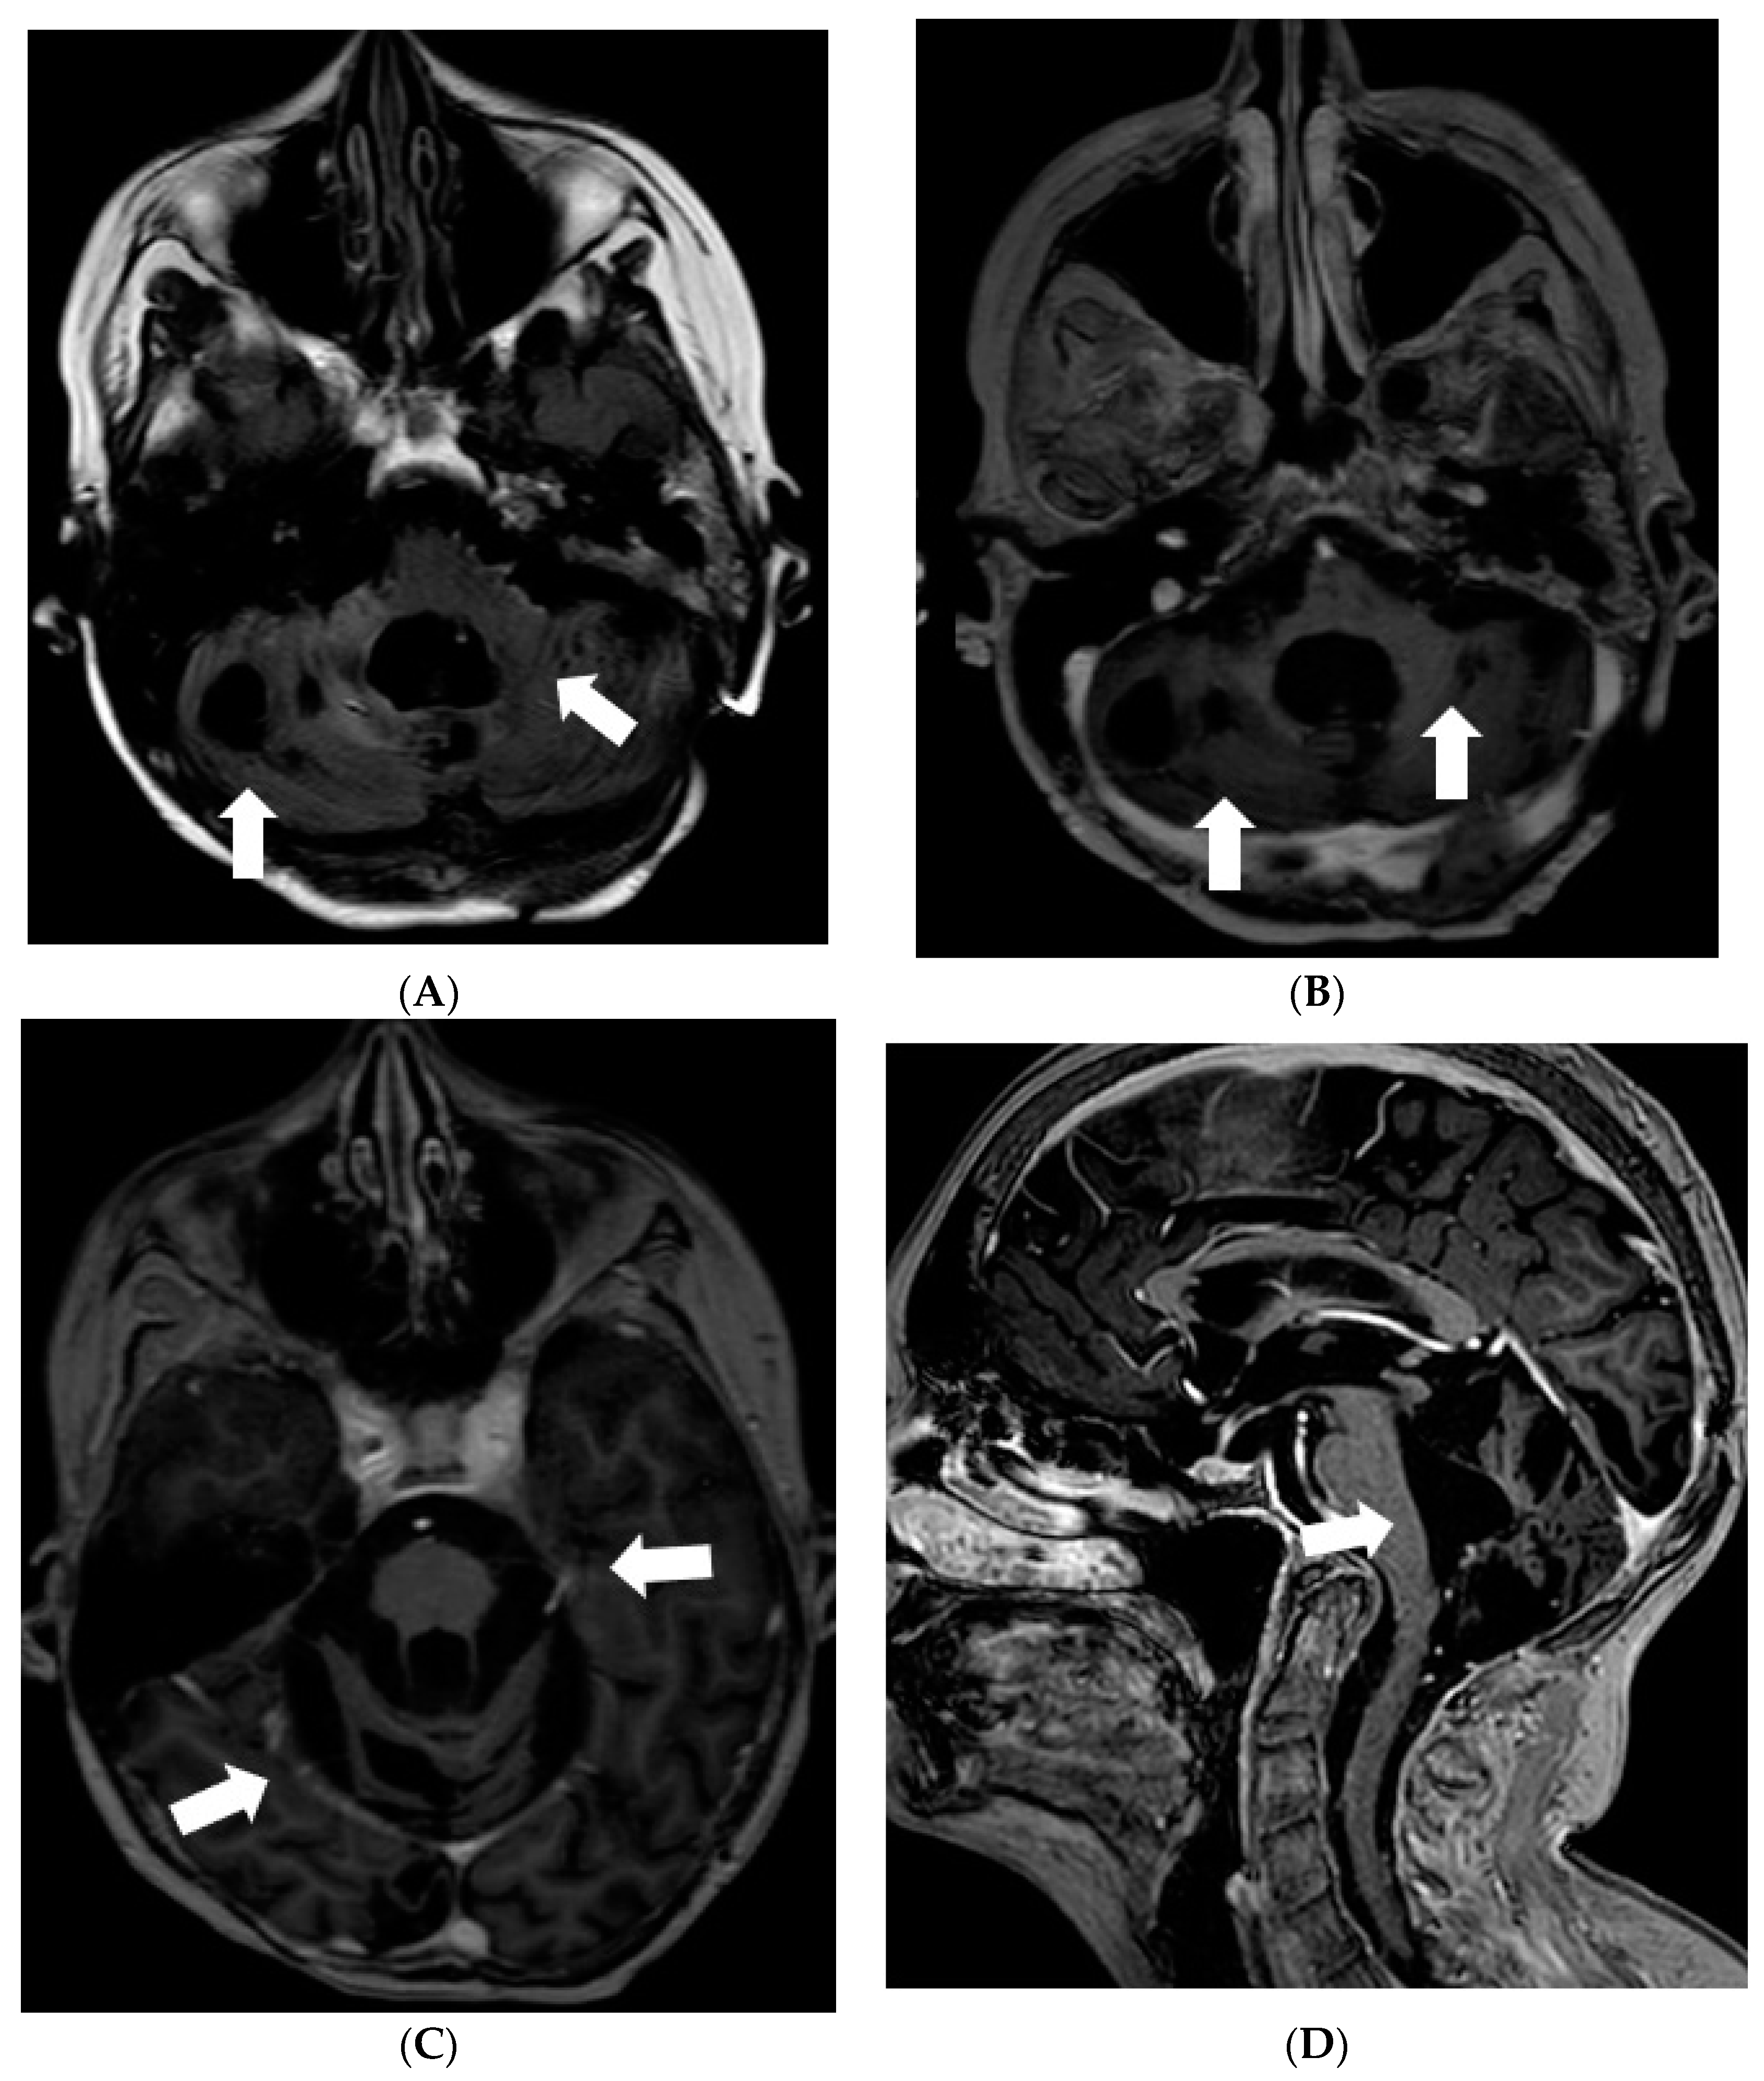

Due to impaired vision, further loss of hearing, and ability to walk, an MRI of the brain and spine was repeated in 2020. MR brain revealed residual changes—cystic leptomeningeal-subpial nodular lesions that were hypointense on T2W/FLAIR, and did not show contrast enhancement in the posterior fossa and along the basal cisterns, surrounding the brainstem, cranial nerves, and cerebellum. Imaging of spinal cord revealed cystic nodular lesions resembling those found in the brain and causing persistent, multisegmental spinal cord compression (Figure 6).

Figure 6.

Follow-up MRI of the brain and spinal cord 9 years after the onset of symptoms (November 2020): (A) Axial T2W/FLAIR, (B,C) and (D) sagittal T1W post-contrast images demonstrate residual non-enhancing cystic lesions in basal cisterns and posterior fossa surrounding brainstem and cerebellum. (D) Sagittal T1W post-contrast image shows diffuse atrophy of the cerebellum. (E,G,I) Sagittal T2W and (F,H,J) T1W post-contrast images of (E,F) cervical, (G,H) thoracic, and (I,J) lumbar spinal cord reveal diffuse intradural extramedullary mixed cystic and solid lesions that show medium contrast enhancement and slight compression of spinal cord at various levels.